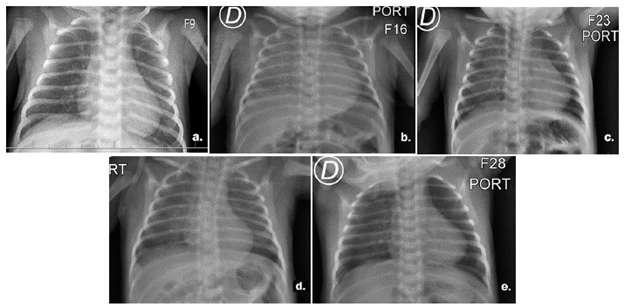

Pasadas las 6 horas postransfusión, el paciente se encontró en regulares condiciones generales, con aspecto séptico e incremento del esfuerzo respiratorio, por lo que se consideró inicialmente una sepsis neonatal tardía de origen viral. Se le realizaron exámenes de control de perfil infeccioso con resultado de procalcitonina negativa, el análisis citoquímico de líquido cefalorraquídeo estuvo dentro de parámetros de normalidad y una serie de radiografías de tórax que inicialmente evidenciaron velamiento en ambos hemitórax con predominio derecho y posteriormente presentó una leve mejoría del patrón radiológico (Figura 1).

Figura 1a estudio normal; 1b. Velamiento en ambos hemitórax con predominio derecho. No se observa derrame pleural; 1c. Edema intersticial parahiliar de predominio derecho; 1d. Edema intersticial parahiliar de predominio derecho. No se observa derrame pleural; 1e. Leve engrasamiento peribroncovascular, silueta cardiaca dentro de límites normales. Ángulos cardiofrénicos y costodiafragmáticos libres.